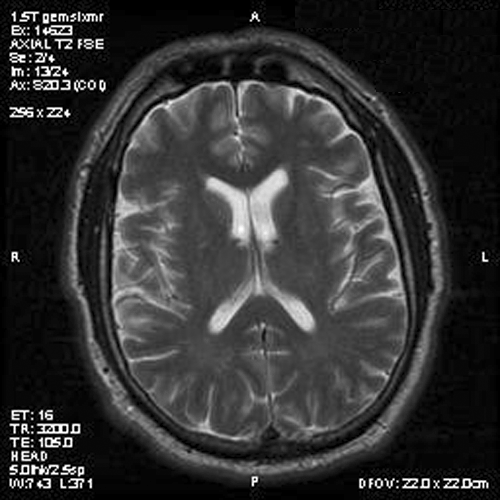

Image of the case: In the left frontal horn there is a well demarcated, subependymal mass measuring approximately 1.1 x 0.5 cm which is relatively hyperintense to white matter on T1-weighted image (Panel A and B) as well as T2-weighted image (Panel C) sequences. It does not enhance on the post contrast images. There is no obstruction of the foramen of Monro.

Typically, subependymoma occur as a fungating mass that protrudes into the ventricle. A mild to sometime significant hydrocephalus can be caused by these tumors. On T1-weighted images, they have intensity similar to that of the surrounding white matter. T2-weighted images usually do not demonstrate significant edema around these tumors. Some of its properties also varies according to the locations. In tumors arising in the fourth ventricle, calcification and heterogeneous contrast enhancement are common; whereas these findings are rare in subependymomas arising in the lateral ventricles 6.